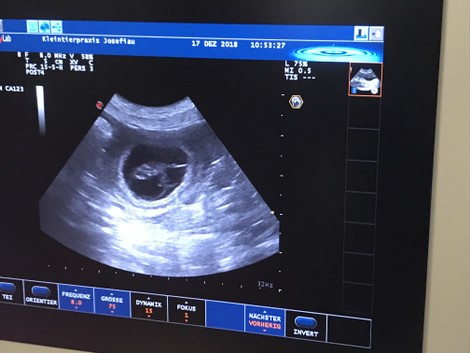

17.12.2018/ Tag 25Im Ultraschall konnten wir zumindest 5 kleine Blasen mit schlagenden Herzen gesehen